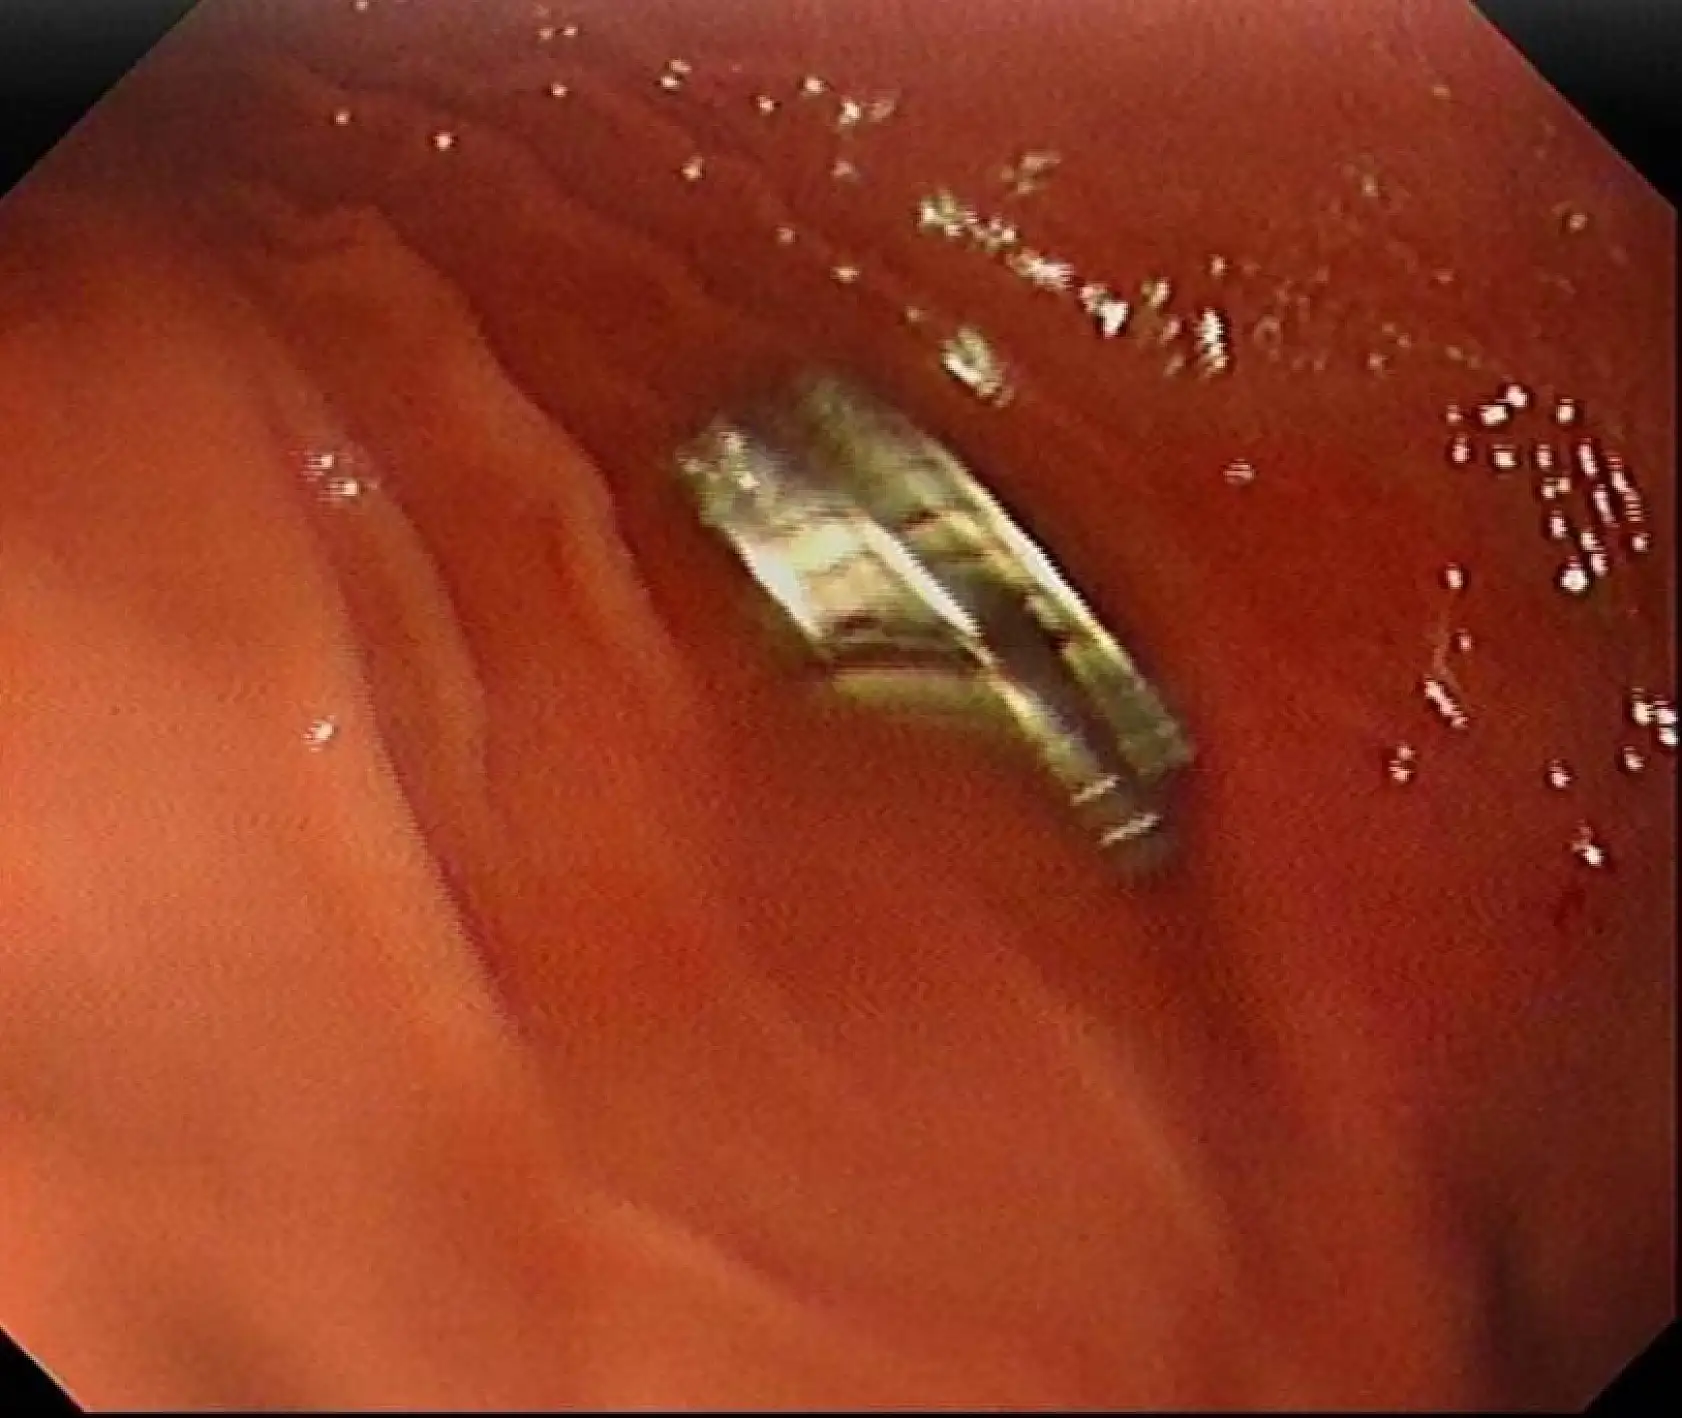

Çocuğun boğazından 19 adet mıknatıs çıkartıldı

3 yaşındaki bir çocuğun yuttuğu 19 mıknatıs, Fırat Üniversitesi Hastanesinde başarılı bir operasyon ile çıkartıldı. Edinilen bilgiye göre, Erzurum'da bir çocuk evde bulunan 19 tane mıknatısı yuttu.